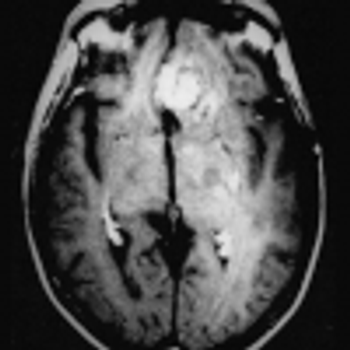

Researchers from Mount Sinai examine and assess the imaging modalities used to evaluate patients positive for the virus.

Affected patients were sicker and more likely to be admitted to the ICU.